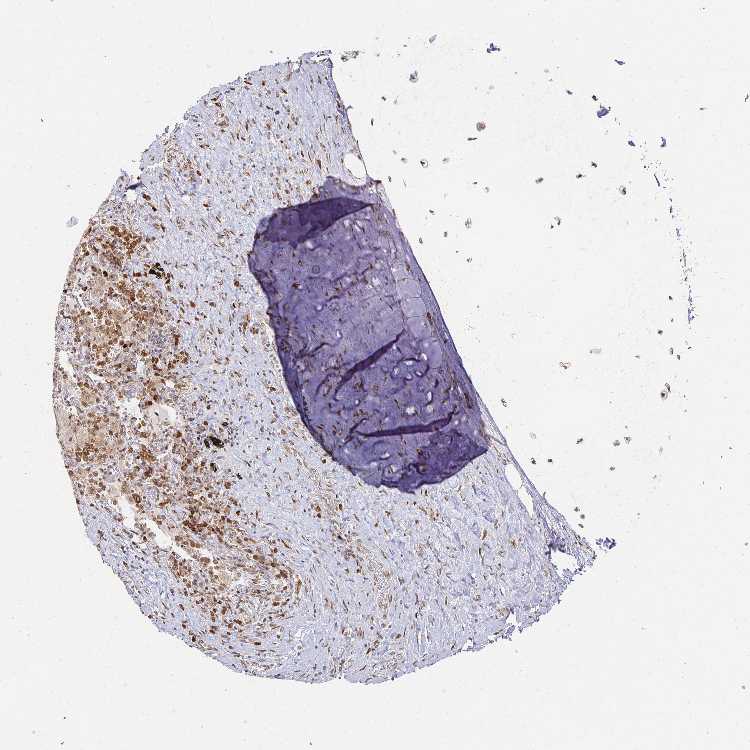

SOFT TISSUE 1 - Antibody stainingi

Antibody staining in the annotated cell types in the current human tissue is reported as not detected, low, medium, or high, based on conventional immunohistochemistry profiling in selected tissues. This score is based on the combination of the staining intensity and fraction of stained cells.

Each image is clickable and will lead to virtual microscopy that enables deeper exploration of all samples and also displays staining intensity scores, fraction scores and subcellular localization as well as patient and tissue information for each sample.

Antibody HPA038875Antibody HPA062281Antibody CAB033750

Chondrocytes Not detectedHigh-

Fibroblasts Not detectedHighMedium

Peripheral nerve Not detected-Medium

SOFT TISSUE 2 - Antibody stainingi

Chondrocytes --Medium

Peripheral nerve Not detectedMediumMedium